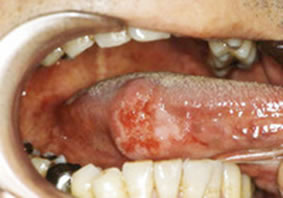

舌癌